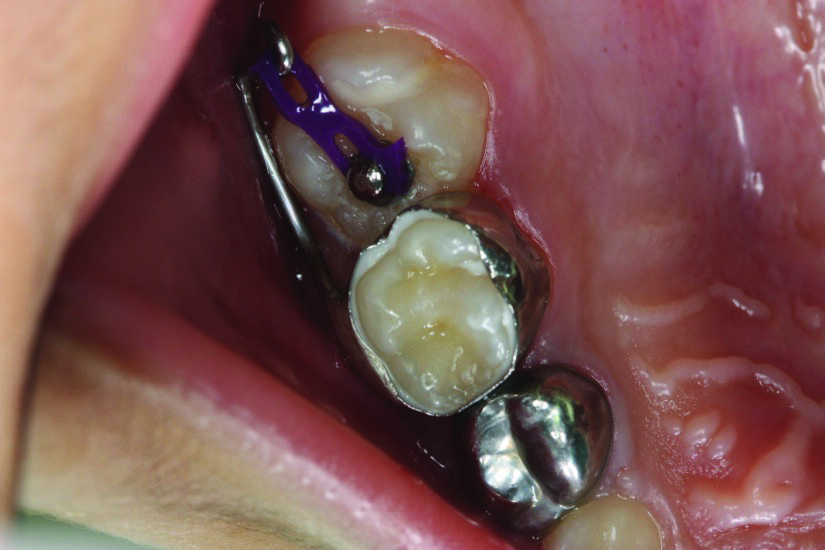

Figure 3: A plastic orthodontic separator is placed to attempt to correct a mild ectopic eruption in the upper right first permanent molar.

Treatment depends on how severe the impaction appears clinically and radiographically. For mildly impacted first permanent molars, where little of the tooth is impacted under the primary second molar, elastic or metal orthodontic separators can be placed to wedge the permanent first molar distally4, Figure 3. For more severe impactions, distal tipping of the permanent molar is required. Tipping action can be accomplished with brass wires, removable appliances using springs, fixed appliances such as sectional wires with open coil springs, Figure 4, sling shot-type appliance3, Figure 5, a Halterman appliance5, Figure 6, or surgical uprighting6.